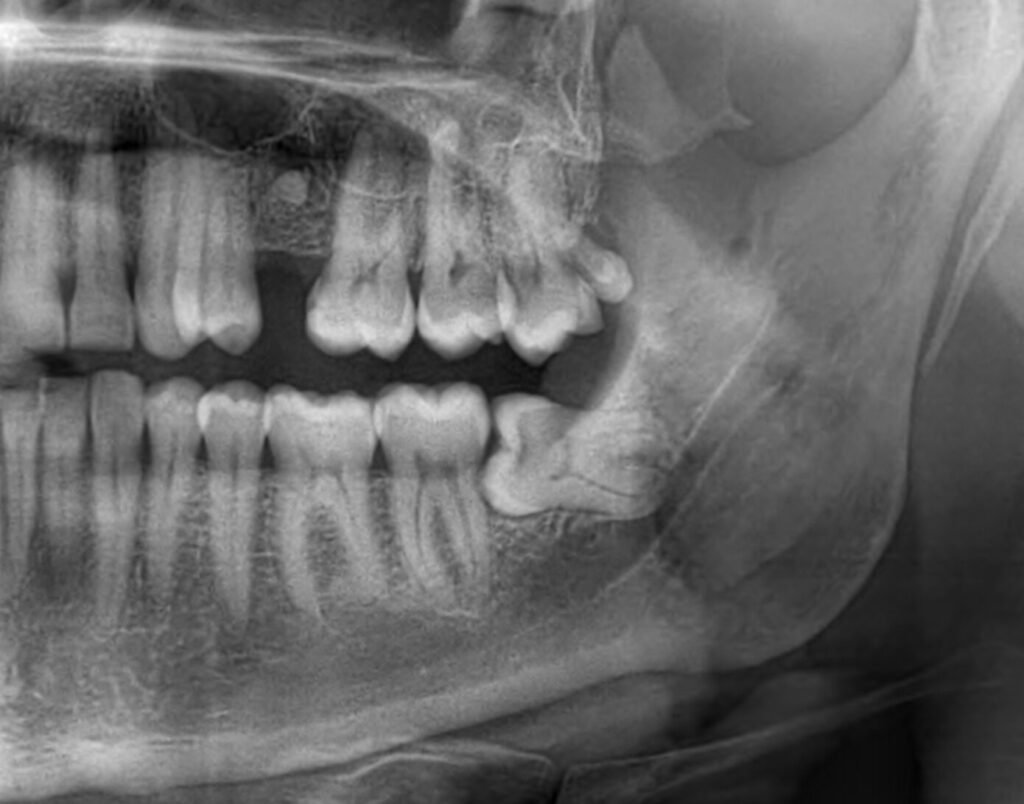

- Valutazione specialistica con radiografie digitali 3D per analizzare la posizione del dente.